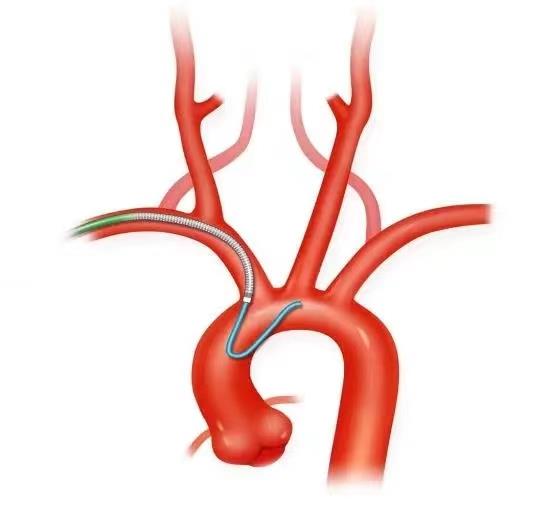

为促进多学科融合发展和诊疗模式的转变,2023年以来,市四医院心血管内科和神经内科联合开展了“冠状动脉+脑血管造影”术,一站式明确患者心脑血管的病情,为进行“心脑一体化诊疗”提供了详细的临床资料,同时联合造影也大大减轻了患者的经济负担和手术痛苦。

心脑同台造影的优点

1.减少手术次数,减轻患者痛苦;

2.降低手术总费用,避免手术一次性使用耗材的浪费;

3.避免反复穿刺、置鞘,导致动脉闭塞;

4.避免了患者反复转科,过程手续繁杂的情况发生。